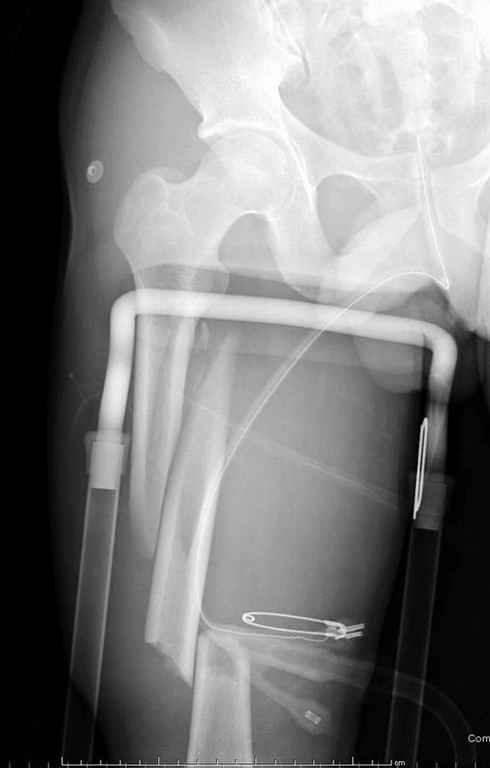

Здесь слайды случая больного с политравмой, включающей сегментарный перелом бедра и повреждение таза с нарушением тазового кольца, разрыв симфиза и перелома крестца зон 2 и 3.

На множественных слайдах важные моменты операции. Хотел бы подчеркнуть, как важно иметь возможности всех необходимых ренгенограмм, включая компютерную томографию и стандартных внутритазовых рентгенограмм (инлет и оутлет).